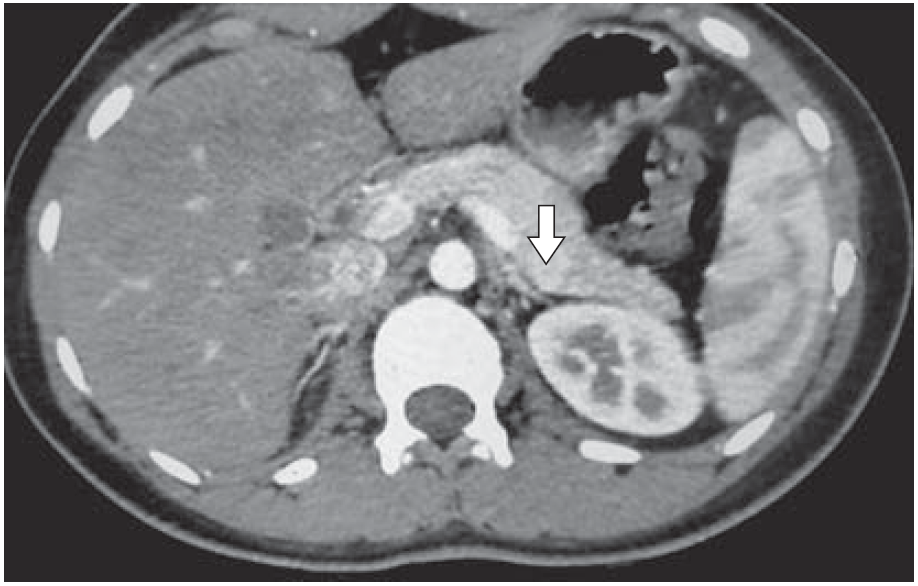

Нами оперированы 8 детей с патологией надпочечников: трое больных с синдромом Гиппеля–Линдау; один ребенок по поводу инциденталомы (по итогам морфологии оказавшейся нейрофибромой); один ребенок по поводу эндотелиальной кисты, один – по поводу первичного гиперальдесторонизма, один – по поводу узелковой гиперплазии коры надпочечников, и одна девочка 16 лет оперирована по поводу адренокортикального рака (рис. 3 а, б). В основном адреналэктомия выполнена лапароскопически, дважды операция выполнена открыто – один больной был с параганглиомой (опухоль располагалась на аорте, что обусловливало крайне высокий риск кровотечения). В случае адренокортикального рака выполнена люмботоракофренулотомия (рис. 4).

Рис. 4. КТ больного с параганглиомой.

Инсулиномы, как правило, представляют собой солитарные, инкапсулированные опухоли небольшого размера (<2 см) и в 98% случаев локализуются внутри ПЖ. Маленький размер опухолей затрудняет их топическую диагностику (рис. 9).

Рис. 9. Девочка Ш., 16 лет. Инсулинома хвоста ПЖ размерами 12 × 10 мм (стрелка).